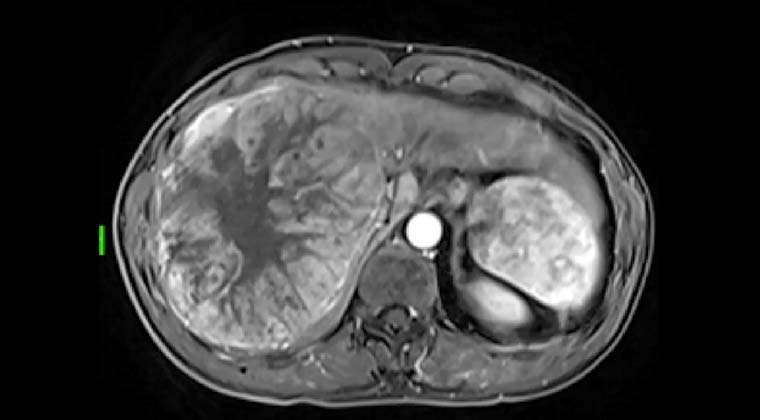

Пациент: мужчина, среднего возраста, гепатоцеллюлярная карцинома

Клиническое течение: Во время профилактического обследования у пациента была диагностирована поздняя стадия гепатоцеллюлярной карциномы, сопровождавшаяся крупной опухолью печени и опухолевым тромбом в воротной вене. Заболевание прогрессировало быстро, качество жизни значительно ухудшилось.

Ход лечения: Пациент обратился в нашу клинику в феврале 2024 года.

Перед лечением была выполнена имитационная оценка с использованием иттрий-90: в артерии, питающие опухоль, был введён MAA с последующим проведением SPECT-сканирования для подтверждения распределения кровотока и границ безопасности. После этого была проведена терапия смоляными микросферами иттрия-90, при которой рассчитанная доза микросфер по плану была введена в опухоль-питающие артерии с обеспечением адекватного покрытия очага.

Ранний послеоперационный период: В раннем послеоперационном периоде отмечались лёгкая слабость, снижение аппетита и субфебрильная температура. После симптоматического лечения данные проявления постепенно регрессировали.

Наблюдение и исход: Контрольные обследования показали выраженное уменьшение размеров опухоли и регресс опухолевого тромба воротной вены. По данным визуализации был отмечен некротический ответ очагов.

После MDT-оценки и подтверждения возможности хирургического вмешательства было выполнено оперативное удаление некротизированной опухоли. По данным патоморфологического исследования подтверждён некроз опухоли. Общее состояние пациента постепенно улучшилось, качество жизни повысилось.

(По данным визуализационных исследований выявлена гигантская опухоль правой доли печени диаметром 16 см)